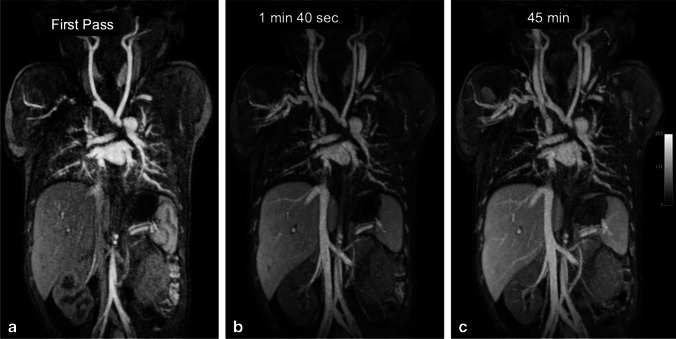

A 3-day-old boy with hypoplastic aortic arch and coarctation. a–c Coronal thin maximum intensity projection images from ferumoxytol-enhanced magnetic resonance angiography in the arterial (a), early venous (b) and late venous (c) phases at 3.0 T. Note the stable intravascular signal in the 43-min interval between the early and late venous phases

Figures 5 and 6 compare two neonatal patients, 2 and 3 days old, respectively. These figures show a noticeable decrease in the intravascular signal with gadofosveset by 2 min, whereas the intravascular signal with ferumoxytol is unchanged after 45 min.